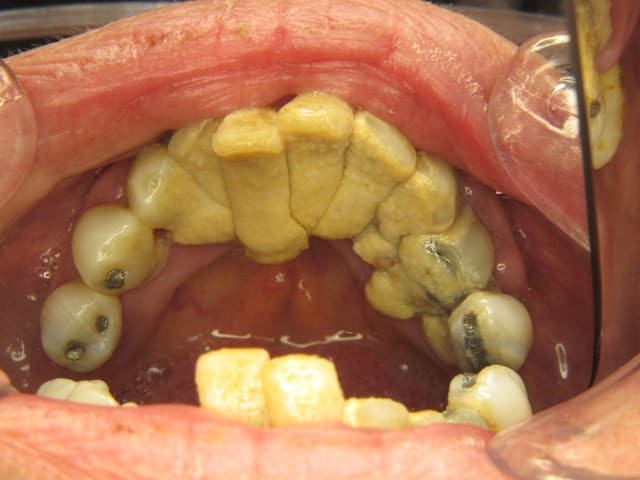

J'ai gagné le concours!!!